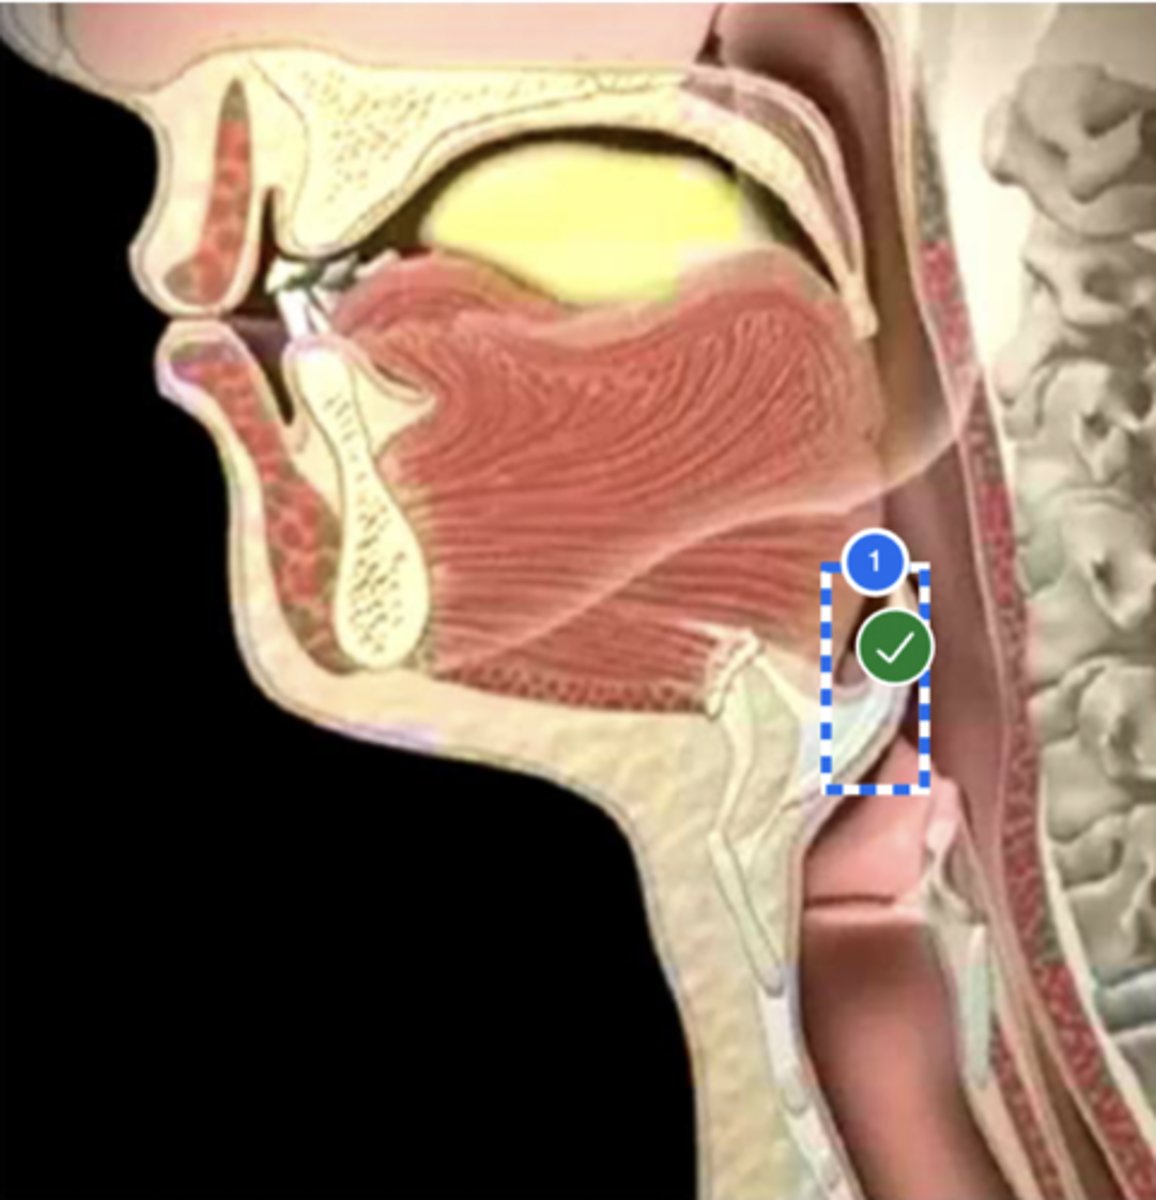

Label base of tongue (lateral view)

label anterior tongue (lateral view)

Label posterior/ back of tongue (lateral view)

Label Mandible (lateral view)

Label velum/ soft palate (lateral view)

Label hyoid bone (lateral view)

Label epiglottis (lateral view)

Label thyroid cartilage (lateral view)

Label posterior cricoid (lateral view)

Label trachea (lateral view)

Label upper esophageal sphincter (lateral view)

Label esophagus (lateral view)

Label posterior pharyngeal wall (lateral view)